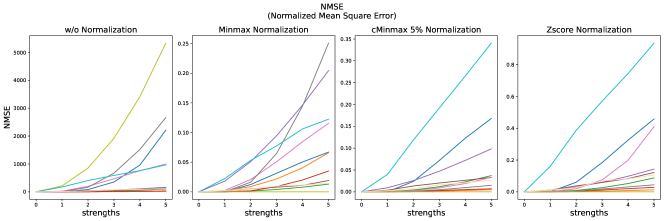

The results for all strengths are given in Figs. A.1-A.4. In Tab. 5 - 8, the results for distortions of maximal strength (s=5) are summarized.

For all applied distortions, all reference metric scores monotonously measure lower similarity for increasing distortion strengths.

Without applying any normalization, all metrics beside NMI are very sensitive to intensity shifts (see Tab. 5). However, with any normalization method, intensity shifts are fully compensated, and all metrics measure perfect similarity.

Across all normalization methods, all metrics are very sensitive to translation and not very sensitive to replace artifacts.

SSIM similarity scores for strong blurring are very high, compared to most other distortions.

Gaussian noise is better detected with Minmax normalization, while stripe artifacts seem to be less detected with Zscore normalization.

PSNR scores generally display only very small changes for strengths larger than 2 (see Fig. A.1). PSNR values are higher for Zscore normalization.

Images distorted with Gaussian blurring and ghosting artifacts receive very high PSNR similarity scores, especially with small distortion strengths.

All error metrics (MSE, MAE and NMSE) strongly vary in their value range, depending on the normalization method. They are consistently most sensitive to translation and then to bias field, and gamma transforms. As cMinMax partially compensates the effect of the gamma transforms, the error metrics hardly find dissimilarities in the gamma transformed images with this normalization.